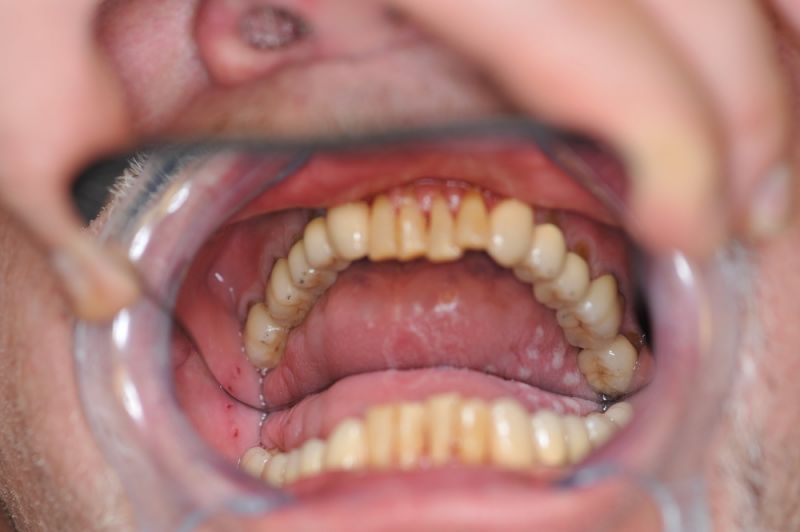

Die funktionstherapeutische Behandlung ist damit abgeschlossen. Der Patient ist vollkommen beschwerdefrei. Beschwerdelevel: "0".

Der Patient ist vollkommen beschwerdefrei!

Es erfolgt engmaschiger vierteljährlicher Recall mit Überprüfung der statischen und dynamischen Okklusion.

Das Weihnachtsgeschenk des Patienten nach zweieinhalb Jahren zahnärztlicher Funktionsdiagnostik und -therapie.

Trotz der langen Behandlungszeit ist der Patient glücklich, dass er die Behandlung absolviert hat, weil er seit Eingliederung des adjustierten Aufbissbehelfs vollkommen beschwerdefrei ist.

Die Idee, es könne sich bei seinen Beschwerden um die Symptome einer CMD handeln, habe er nur durch Zufall bekommen und bedauert, dass es das nicht schon viel früher gewusst habe.

So viel zur Frage, ob sich eine derart aufwändige Behandlung bei einem damals 78 jährigen Patienten überhaupt noch "lohne"!